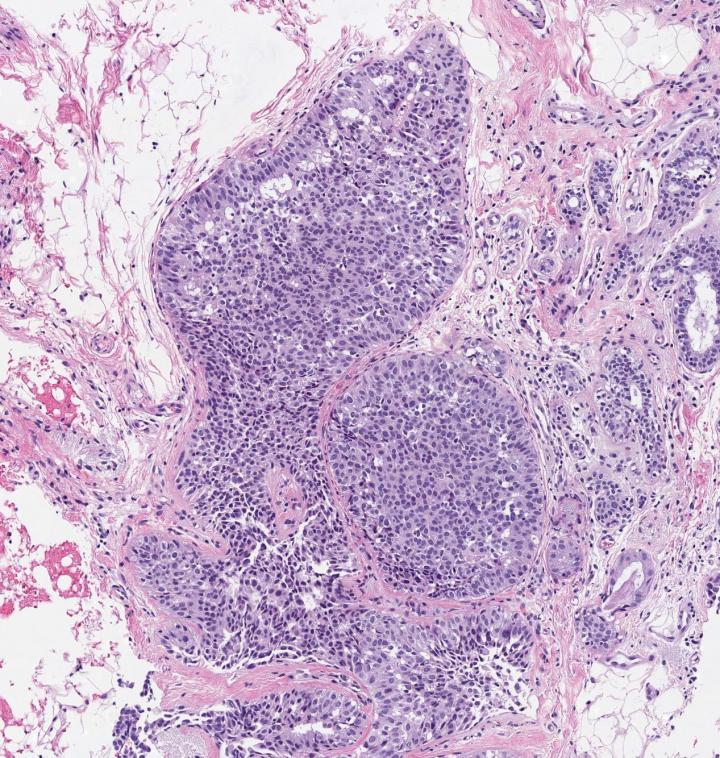

image: A microscopic image of breast tissue showing proliferative benign breast disease, including abnormal cells view more

Credit: Hospital del Mar Medical Research Institute, Barcelona, Spain

They also classified the BBDs as non-proliferative or proliferative, depending on whether or not the breast tissue showed an increase in the growth of certain cells, such as the ductal cells found in ductal hyperplasia in which there is an overgrowth of cells lining the ducts inside the breast.